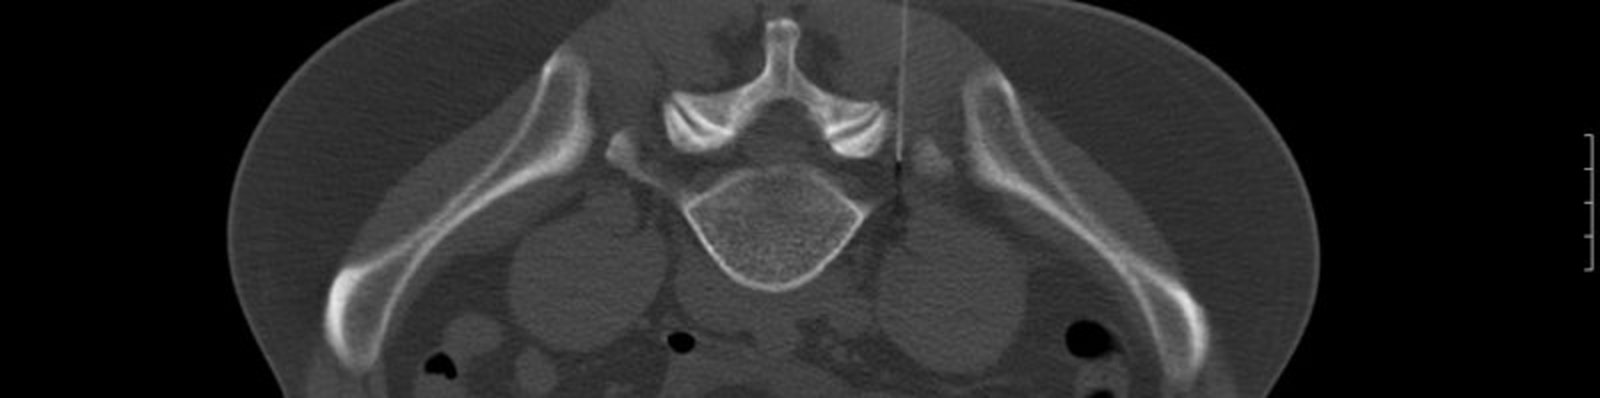

CT-gesteuerte Interventionen

Aus personellen Gründen können wir diese Leistungen ab dem 01.01.2023 nicht mehr anbieten.